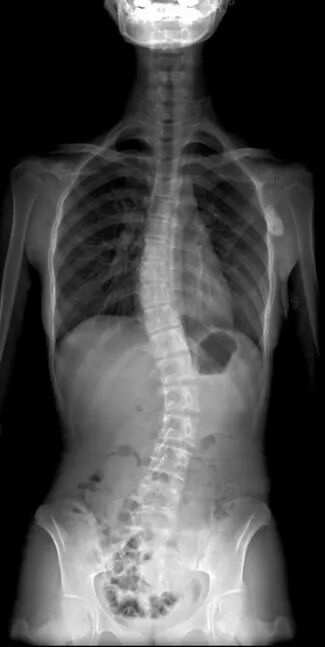

岛津大平板多功能机 C200 搭载的 SLOT 功能,有效解决了儿童脊柱检查中的痛点,为儿童脊柱侧弯筛查提供了高效、可靠、准确的技术方案。该功能通过单次连续扫描即可完成全脊柱影像数据采集,并依托设备内置的智能拼接算法,自动生成完整、连贯的全脊柱影像,无需人工二次处理。在临床应用中,儿童仅需保持短时间卧位或立位即可完成检查,大幅降低了体位配合难度;生成的影像分辨率高,可清晰呈现脊柱椎体形态、椎间隙结构及侧弯细节,即使是轻度侧弯也能精准识别,为早期诊断提供可靠依据。

SLOT功能采集的脊柱图像